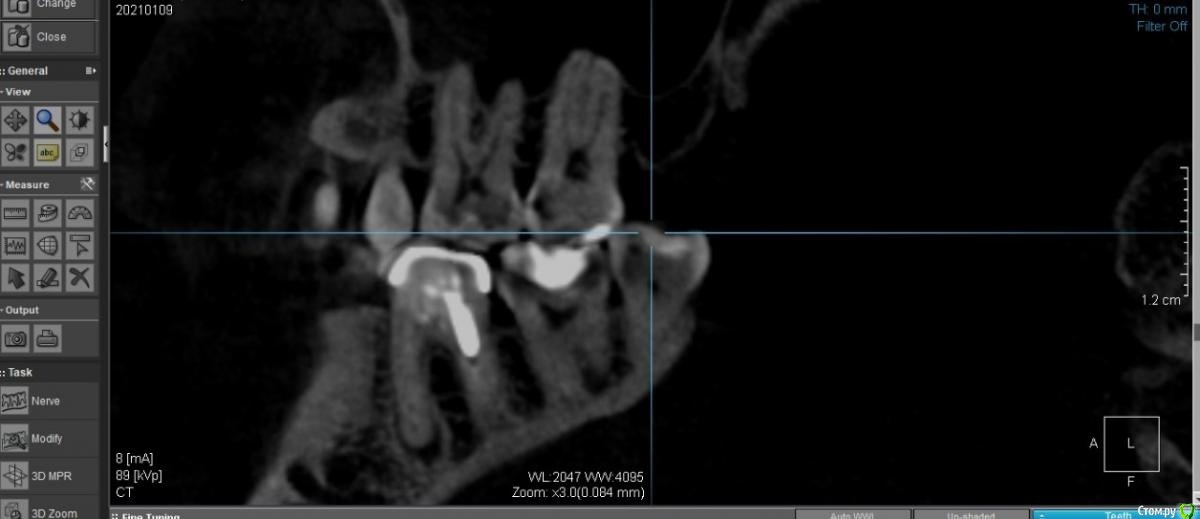

Serpla Опубликовано 24 февраля, 2021 Поделиться Опубликовано 24 февраля, 2021 Добрый день,случайно на КТ обнаружили кисту. Плюс подозрение на разряжение ткани в области бифуркации.Это все под коронкой, установленной 15+ лет назад.Стоит ли пытаться перелечить или выход - удаление + имплант?Сколько зуб протянет, если ничего не делать (3й вариант)Спасибо Ссылка на комментарий

Nazim_NV86 Опубликовано 2 марта, 2021 Поделиться Опубликовано 2 марта, 2021 Это не киста, если называть вещи своими именами. 1 Ссылка на комментарий

Irouil Опубликовано 2 марта, 2021 Поделиться Опубликовано 2 марта, 2021 Лучше всего спросить у терапевтов На мой взгляд лечение малопрогнозируемо, и "киста" тут не причём Ссылка на комментарий

St. Опубликовано 2 марта, 2021 Поделиться Опубликовано 2 марта, 2021 +1 за лечение. ну или пока ничего не делать в крайнем случае как временный вариант...Показаний к удалению на этом снимке не увидела. Ссылка на комментарий